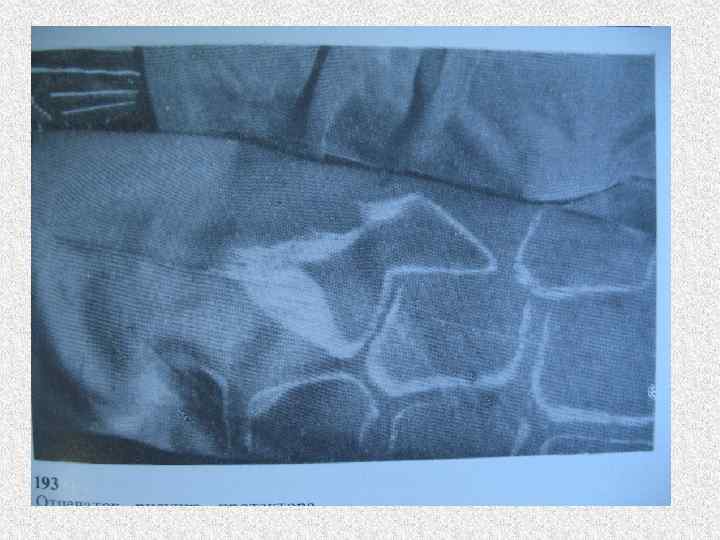

Удар решеткой радиатора